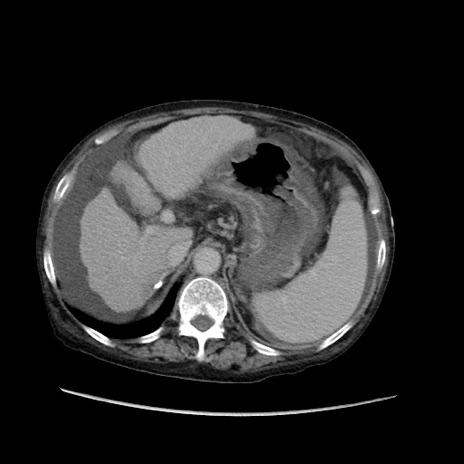

症例31(横断像)

【症例】80歳代 女性

【主訴】腹部膨満感

【現病歴】他院にて肝硬変にてフォロー中。1週間前から便秘、腹部膨満感、臍部腫瘤あり受診となる。

【既往歴】肝硬変

【身体所見】腹部膨隆あり、皮膚変化なし、疼痛なし。

【データ】WBC 4600、CRP 0.25